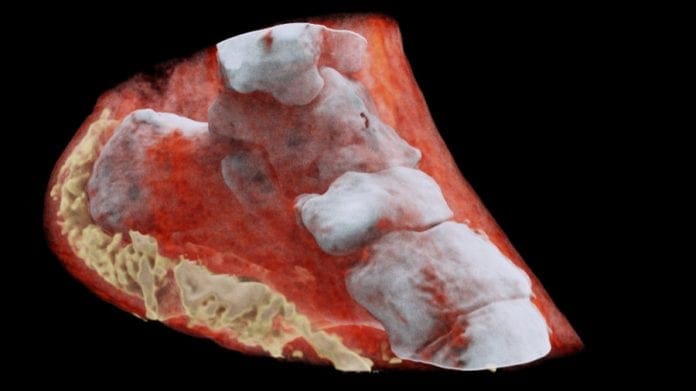

Компанијата од Нов Зеланд Mars Bioimaging е првата компанија која започна да нуди рендген снимки и други компјутерски снимања за медицински цели, во боја и во 3D. За разлика од моменталните црно бели слики кои сите ги знаеме од посетата на доктор некогаш во нашиот живот, новите слики во боја треба да овозможат многу подобри детали и можност за докторите да проценат што не е во ред, доколку тоа е случајот.

Новиот систем за скенирање е наречен Spectral CT, а она што привлекува дополнително внимание е како истиот е развиен. Тој е направен благодарение на програмата на CERN за споделување на знаењето, односно на технологиите кои тие специјално ги развиваат за нивните потреби.

Spectral CT системот е направен на основа на чипот Medipix3 кој во CERN е развиен за потребата за детално истражување на честичките, нешто што е основа работа на овој институт. Чипот овозможува да се добие детална слика во висока резолуција од светлината што ја враќа секоја честичка и паѓа на секој посебен пиксел на апаратот за скенирање.

Овој систем овозможува да прикаже детална слика од коските, од мускулите, меките ткива, а како што се гледа на една од сликите, прикажан е и часовникот на човекот чиј зглоб од раката се скенира.